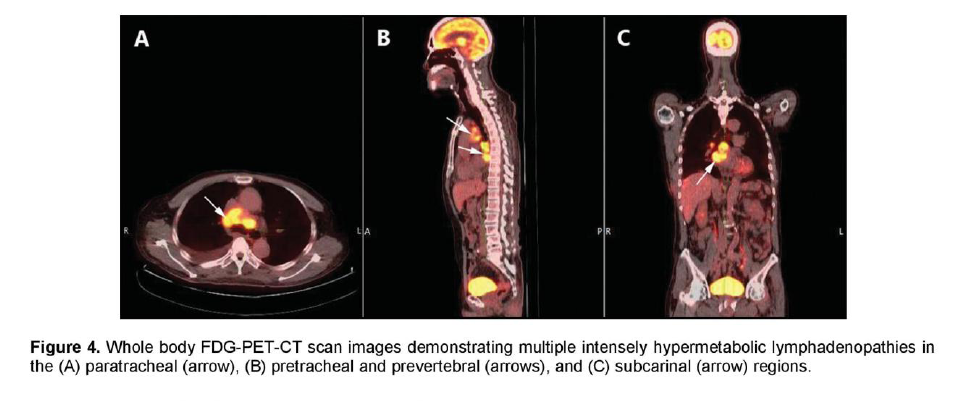

There was a mildly enhancing 1.3 x 1.3 cm mass in the right temporal lobe with FDG uptake similar to that of white matter. The previously seen mediastinal and right hilar lymphadenopathies had intense FDG uptake with standardized uptake value (SUV) up to 7.3 g/ml (Figure 4). In contrast, the previously noted reticular ground glass opacities in both lungs had low-grade uptake on PET. There were multiple hypermetabolic lesions in both hepatic lobes with SUV up to 5.4 g/ml (Figure 5) which appeared normal on the initial CT scan. A 24-hour urinary 5-hydroxyindoleacetic acid (5HIAA) was four times elevated, indicative of tumor secretory activity. He underwent chemotherapy with Carboplatin, Etoposide and Topotecan and radiation therapy with complete disappearance of the brain lesion but with further derangement in liver function.

Figure 4. Whole body FDG-PET-CT scan images demonstrating multiple intensely hypermetabolic lymphadenopathies in the (A) paratracheal (arrow), (B) pretracheal and prevertebral (arrows), and (C) subcarinal (arrow) regions.